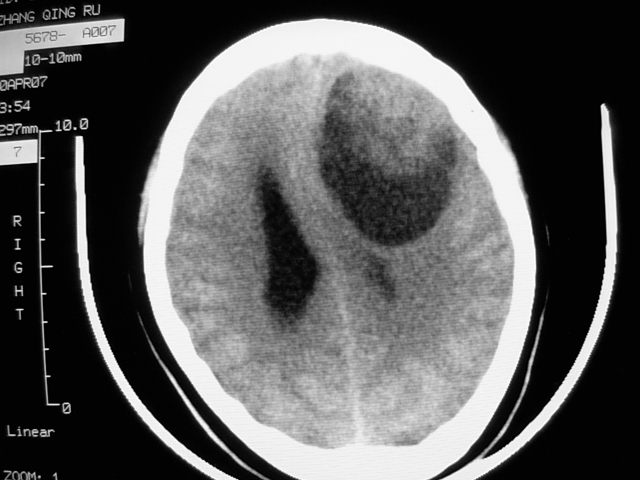

f39y,头疼、眩晕。患者拒绝强化。

左额叶见一巨大椭圆形略低、低密度混杂密度肿块,边界清楚,似与侧脑室额角相通,明显占位效应,左侧侧脑室受压变形,右侧侧脑室扩大,中线结构向右明显弧形移位。鞍上池闭塞。

考虑:1、左额叶良性占位性病变,以皮样囊肿可能性大,伴镰下疝。

肿瘤不再脑室内,左侧的脑室受压了;从平扫考虑两种可能:1.脑膜瘤;2.囊型胶质瘤。

感觉病灶位于侧脑室前角内,而体部受压,病灶形态同前角一致,右侧脑室前角变形并不太严重,病灶呈混杂密度,考虑皮样囊肿或室管膜瘤可能性大一些。

病灶前外侧似可见软组织密度影,考虑囊性星形细胞瘤,建议增强或mr.